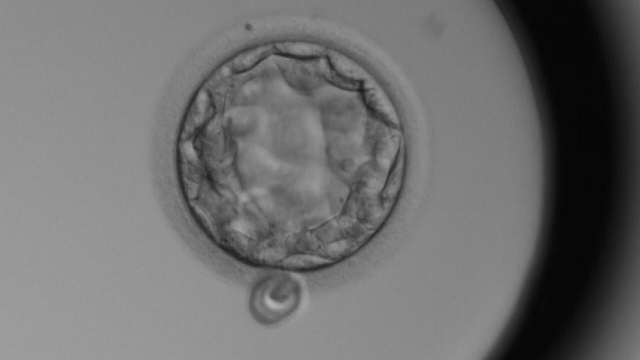

第三者精子提供の行方

不妊大国と言われる日本。最新の研究によると男性の4人に1人が”不妊のリスク”を抱えているという。子どもができない夫婦の最後の選択肢となっているのが精子提供。日本の医療機関では、70年以上前から夫以外の第三者の精子を使った不妊治療が行われてきましたが、いま継続の危機に直面しています。男性不妊、その先にある現状を取材しました。